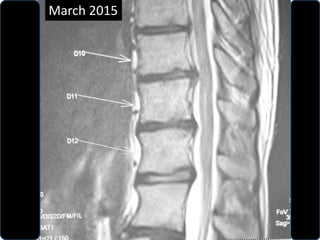

• Follow up MRI was done March 2015

• Complete absorption of fragmant.

March 2015

D10 – D11

D11